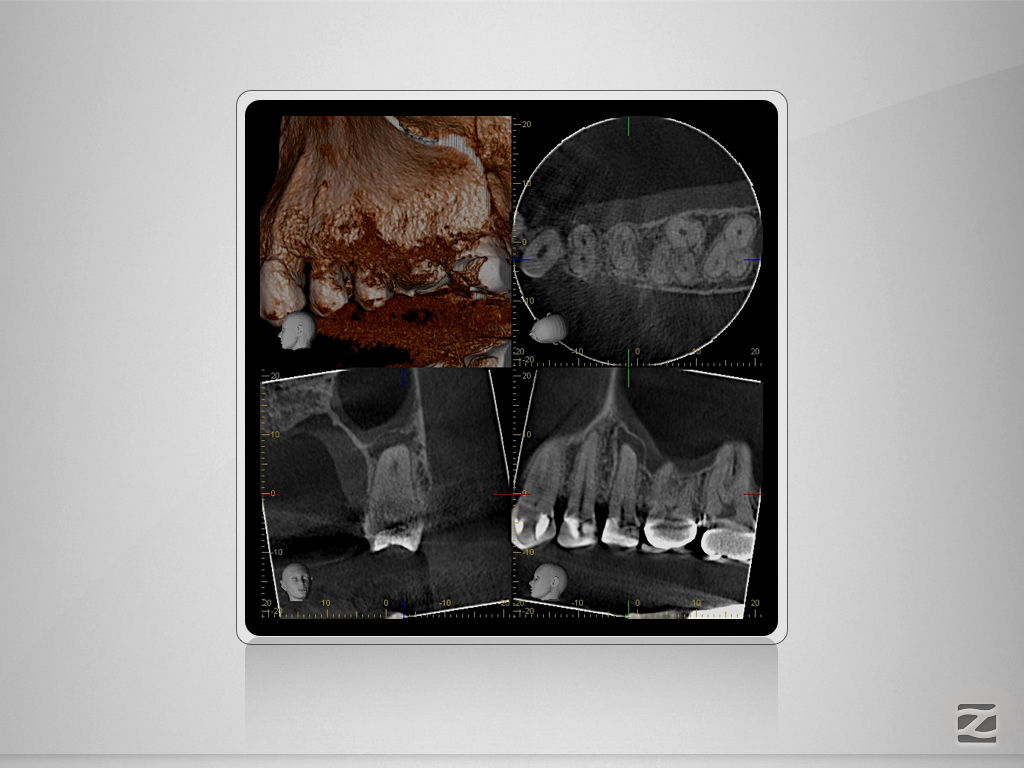

25D.003

Tiefe Gabelung